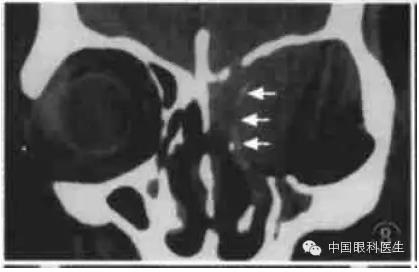

10.甲状腺相关眼病

甲状腺相关眼病也称Graves'病,这是最常见的单侧和双侧眼球突出原因。临床上有眼睑退缩、上睑迟落等一些典型体征。而CT在疾病的不同时期显示出不同的形态学的改变,主要CT征包括:眼球突出、眼外肌肥厚、脂肪垫扩大,其中以眼外肌肥厚最常见(图12)。其受累频率依次是下直肌、内直肌、上直肌和外直肌,晚期提上睑肌、上斜肌均肥厚。甲状腺相关眼病的眼外肌肥厚特征为以肌腹梭形肥厚为主,边界清楚。但当下直肌肥厚做水平CT扫描时,易误诊为眶内肿瘤,此时应做冠状CT鉴别。

图12甲状腺相关眼病CT显示双侧内外直肌肌腹和眶尖部增厚,视神经受压,筛骨纸板向内移位(箭头)